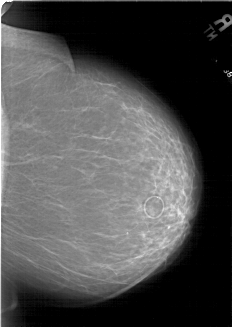

A_1801_1.LEFT_CC

LEFT_CC LINES 6871 PIXELS_PER_LINE 4906 BITS_PER_PIXEL 12 RESOLUTION 43.5 OVERLAY

FILE: A_1801_1.LEFT_CC.OVERLAY

TOTAL_ABNORMALITIES 1

ABNORMALITY 1

LESION_TYPE MASS SHAPE LOBULATED MARGINS CIRCUMSCRIBED

ASSESSMENT 4

SUBTLETY 5

PATHOLOGY BENIGN

TOTAL_OUTLINES 1

BOUNDARY